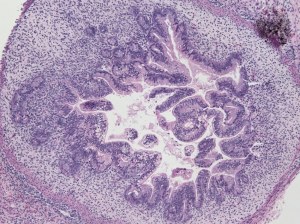

Custom service: Teratoma Formation Assay

A gold standard method to characterize pluripotency of human and mouse ES/iPS cells. => Quote request